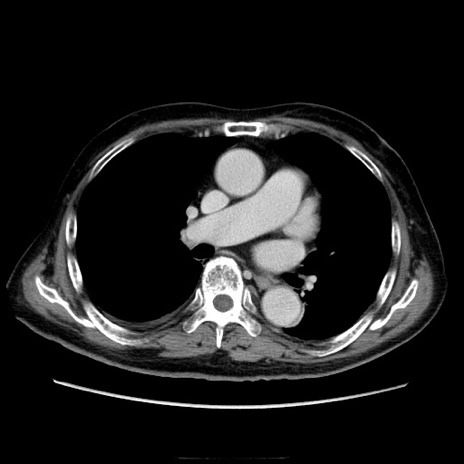

冠状断像

症例21(横断像)

【症例】70歳代男性

【現病歴】肝硬変・肝細胞癌にてかかりつけの方。約9時間前に食後より腹痛出現。症状が徐々に増悪し、嘔吐出現したため来院。

【既往歴】肝硬変、肝細胞癌(RFA、TACE後)